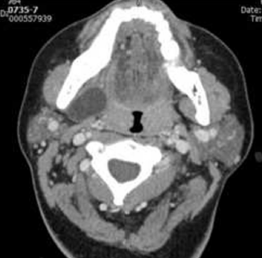

Quiste dermoide latero cervical

18               en el espacio submandibular. Objetivo: Reporte de caso y revisión de la literatura. Caso

19               Clínico: Se presenta un caso de una paciente de 32 años, con un cuadro de 1 año de

20               evolución caracterizado por una lesión de crecimiento lento pero sostenido. Se le realizó la

resección de la lesión junto con una submandibulectmía ipsilateral resultando compatible

23               con un quiste dermoide. Discusión: La localización de esta lesión es muy infrecuente. En el

24               estudio histopatológico son lesiones con epitelio pluri estratificado cornificado y anexos

25               cutáneos. El estudio de imágenes orienta a una lesión quística, siendo la resonancia nuclear

recidivas reportadas cuando la resección ha sido completa.